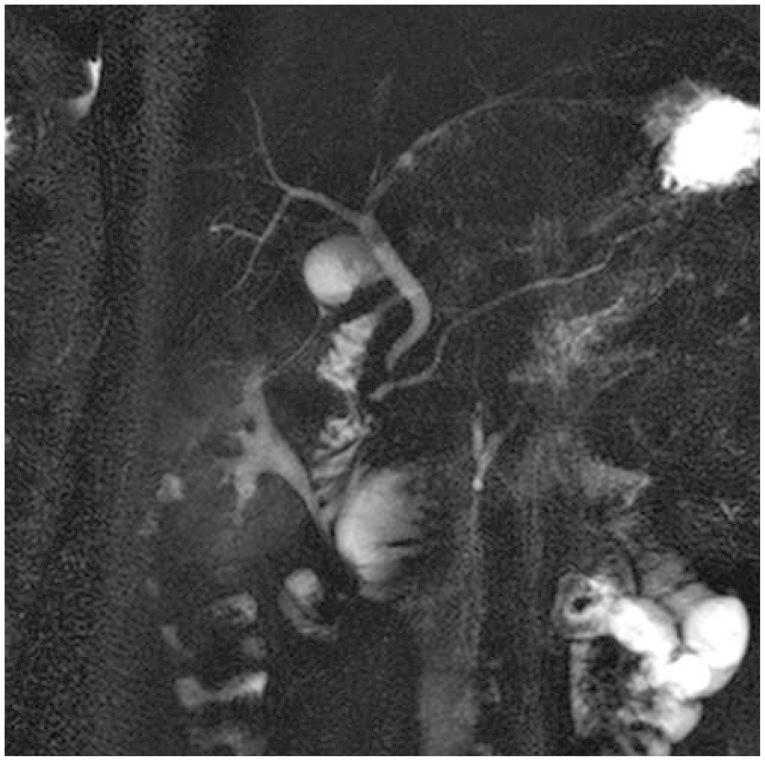

Acute pancreatitis due to a duodenal ulcer.

Duodenal ulcers and acute pancreatitis are two of the most commonly encountered gastrointestinal diseases among the general population. However, duodenal ulcer-induced pancreatitis is very rarely reported worldwide. This report elaborates on a distinct medical treatment that contributes to partial or complete treatment of acute pancreatitis induced by a duodenal ulcer scar.